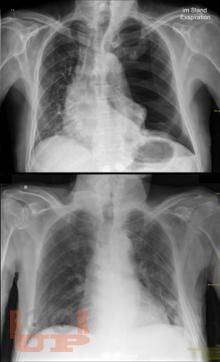

Спонтанный пневмоторакс

Ханнанов Н. И. Спонтанный пневмоторакс : учебное пособие для врачей / Н. И. Ханнанов, В. В. Фаттахов, М. Н. Насруллаев. - Казань : КГМА, 2020. - 40 c. - Текст : электронный // ЭБС "Букап" : [сайт]. - URL : https://www.books-up.ru/en/book/spontannyj-pnevmotoraks-16035604/ (дата обращения: 01.05.2026). - Режим доступа : по подписке.